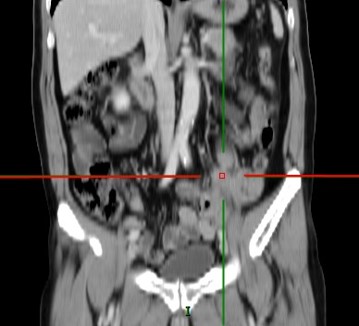

(2019-01-15)全腹+胸部增强CT:左输尿管中段管腔内及其前下方软组织肿块并强化,病灶范围较前稍增大,考虑转移(较大截面约23×22mm);伴其以上左输尿管、左肾盂、肾盏扩张积液较前稍明显。

2019-01-15 腹部CT: